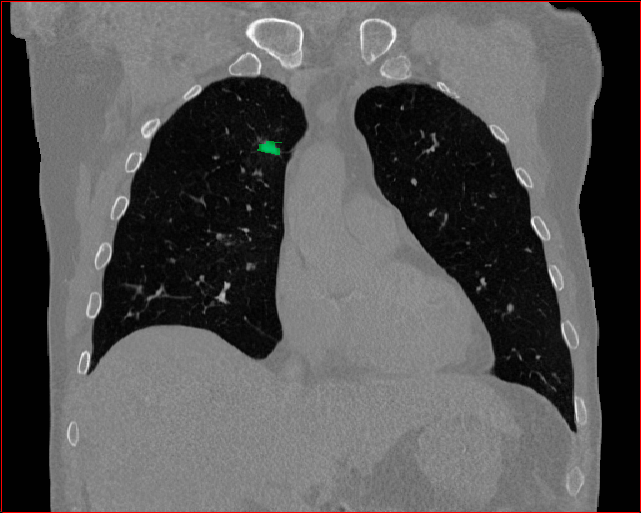

Figure 5 shows qualitative results for MAISI-v2 Controlnet on 5 types of tumors.

Lung Tumor

0.75×0.75×0.60.75\times 0.75\times 0.6

mm

512×512×512512\times 512\times 512

Figure 5: MAISI-v2 segmentation-guided results for five types of tumors. We show results for different voxel spacing and volume size to demonstrate the flexibility of MAISI-v2. Different Hounsfield Unit window is used to better show the contrast between tumor and normal tissues.